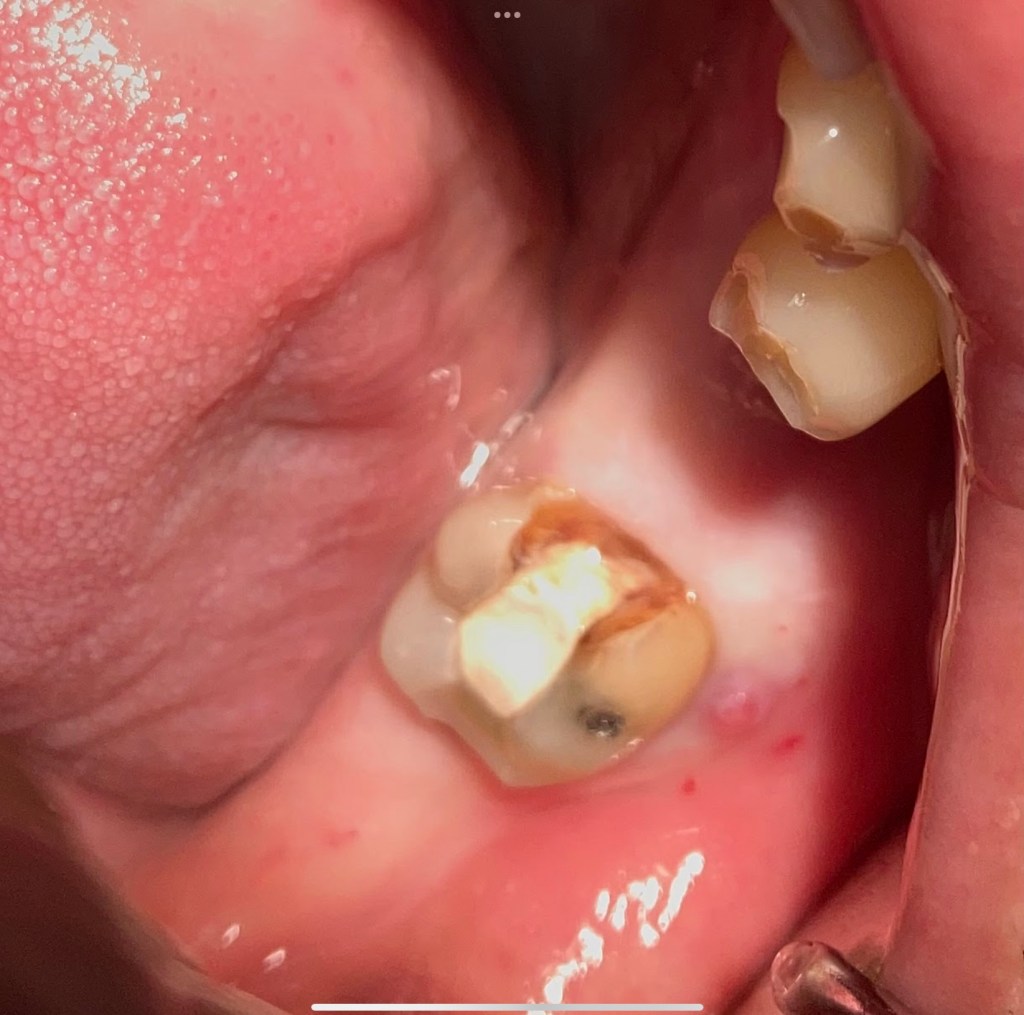

Don’t Remove. (before X-ray) radix-ento พบได้ในคนไทย 12.7% Germination X-ray ช่วยให้เห็นสิ่งที่ซ่อนอยู่ภายใน สังเกต furcation ก็รู้ว่าฟัน Perio Mermaid Premolar ให้สังเกตที่ mouth mirror เห็นถึงความฝ้ามัว เป็น Br พม่าครับ alloy ไม่แข็งมาก X-ray เท่านั้นจึงจะรื้อได้ ผมจะชอบวัดความยาวของฟันบ่อยๆ เทียบกับความยาวในใจที่เดาเอาไว้ RCT incomplete ใครสังเกตเห็นความผิดปกติบ้างครับ? ถึงกับต้องถ่ายทุกมุมเลยซี่นี้ remove ฟัน Crowding เป็น PVC ล้อมด้วยฟัน RCT อย่าลืม X-ray ก่อนถอนนะครับ Share this: Share on X (Opens in new window) X Share on Facebook (Opens in new window) Facebook Like Loading... Uncategorized